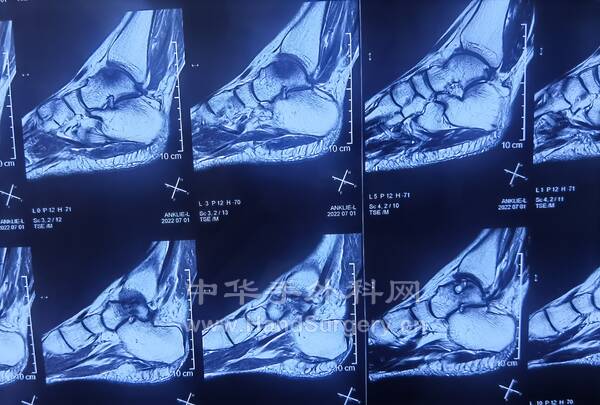

明日需要手术的右足马蹄外翻足,扁平足小患者资料(图18--41)

明日需要手术的右足马蹄外翻足,扁平足小患者资料(图1-24)